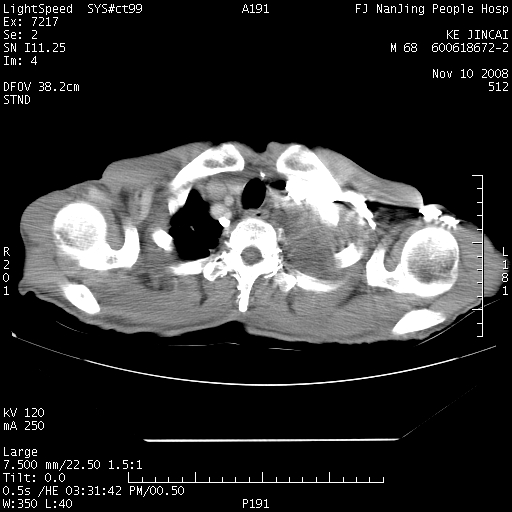

是个很有看头的病例,咋人气那么不旺?没多少人兴趣呢?这个病例几大怪:1   恶性肿瘤侵犯心肌左房怪,心肌一般不会被恶性肿瘤侵犯吧?2   左下肺均匀实变怪,内无含气,有别一般不张实变,含气肺泡完全为液体取代,而非一般不张实变的肺萎陷,冷不丁还以为是肿大的脾脏3   肿瘤本身怪,像tb肺不张4   这么有看头的病例没人气怪。呵呵。

左肺恶性肿瘤侵犯肺动脉,左心房内瘤栓,胸膜转移。

左肺恶性肿瘤侵犯肺动脉,左心房内瘤栓,胸膜转移,少见,学习了。